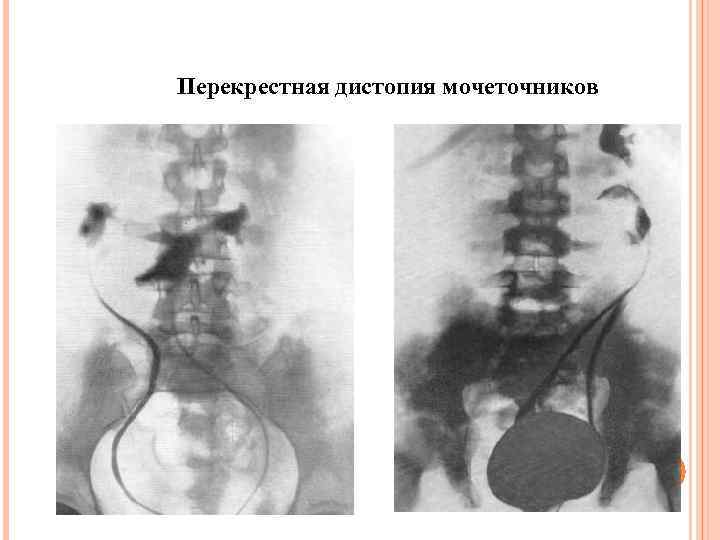

Перекрестная дистопия мочеточников

Перекрестная дистопия мочеточников